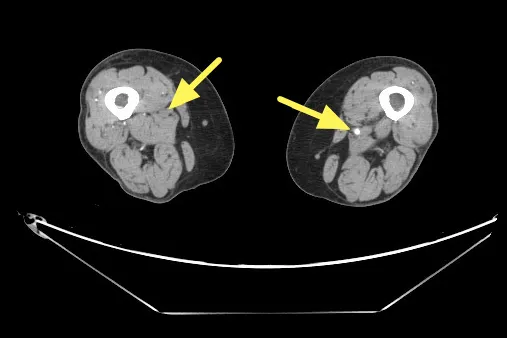

電腦斷層血管攝影顯示右股動脈脈阻塞。聯新醫院提供

楊凱迪指出,近期診治一位64歲長期洗腎的女性患者,數月來反覆出現下肢刺痛,夜深與洗腎後特別明顯,同時右小腿與腳踝各有一處約3x5公分久未癒合的慢性傷口。整形外科醫師清創時發現傷口幾乎沒有出血,轉介心臟血管外科,經「踝臂血壓指數(ABI)檢查」左右腳分別為僅約0.67及0.64,代表下肢血流循環不良。電腦斷層血管攝影更顯示雙側股動脈及膕動脈嚴重狹窄。